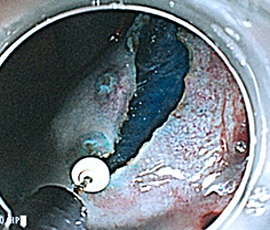

粘膜全周切開

粘膜下層剥離